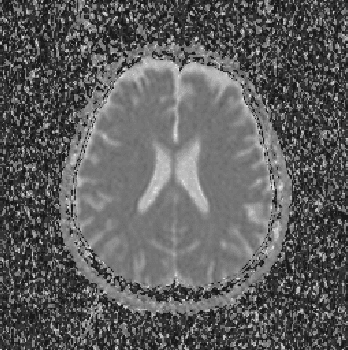

Abstract:Alzheimer's disease is the most common cause of dementia, yet difficult to accurately diagnose without the use of invasive techniques, particularly at the beginning of the disease. This work addresses the classification and analysis of multispectral synthetic images composed by diffusion-weighted magnetic resonance brain volumes for evaluation of the area of cerebrospinal fluid and its correlation with the progression of Alzheimer's disease. A 1.5 T MR imaging system was used to acquire all the images presented. The classification methods are based on multilayer perceptrons and classifiers of radial basis function networks. It is assumed that the classes of interest can be separated by hyperquadrics. A polynomial network of degree 2 is used to classify the original volumes, generating a ground-truth volume. The classification results are used to improve the usual analysis by the map of apparent diffusion coefficients.

Abstract:Alzheimer's disease is the most common cause of dementia, yet hard to diagnose precisely without invasive techniques, particularly at the onset of the disease. This work approaches image analysis and classification of synthetic multispectral images composed by diffusion-weighted magnetic resonance (MR) cerebral images for the evaluation of cerebrospinal fluid area and measuring the advance of Alzheimer's disease. A clinical 1.5 T MR imaging system was used to acquire all images presented. The classification methods are based on multilayer perceptrons and Kohonen Self-Organized Map classifiers. We assume the classes of interest can be separated by hyperquadrics. Therefore, a 2-degree polynomial network is used to classify the original image, generating the ground truth image. The classification results are used to improve the usual analysis of the apparent diffusion coefficient map.

Abstract:Multispectral image analysis is a relatively promising field of research with applications in several areas, such as medical imaging and satellite monitoring. A considerable number of current methods of analysis are based on parametric statistics. Alternatively, some methods in Computational Intelligence are inspired by biology and other sciences. Here we claim that Philosophy can be also considered as a source of inspiration. This work proposes the Objective Dialectical Method (ODM): a method for classification based on the Philosophy of Praxis. ODM is instrumental in assembling evolvable mathematical tools to analyze multispectral images. In the case study described in this paper, multispectral images are composed of diffusion-weighted (DW) magnetic resonance (MR) images. The results are compared to ground-truth images produced by polynomial networks using a morphological similarity index. The classification results are used to improve the usual analysis of the apparent diffusion coefficient map. Such results proved that gray and white matter can be distinguished in DW-MR multispectral analysis and, consequently, DW-MR images can also be used to furnish anatomical information.